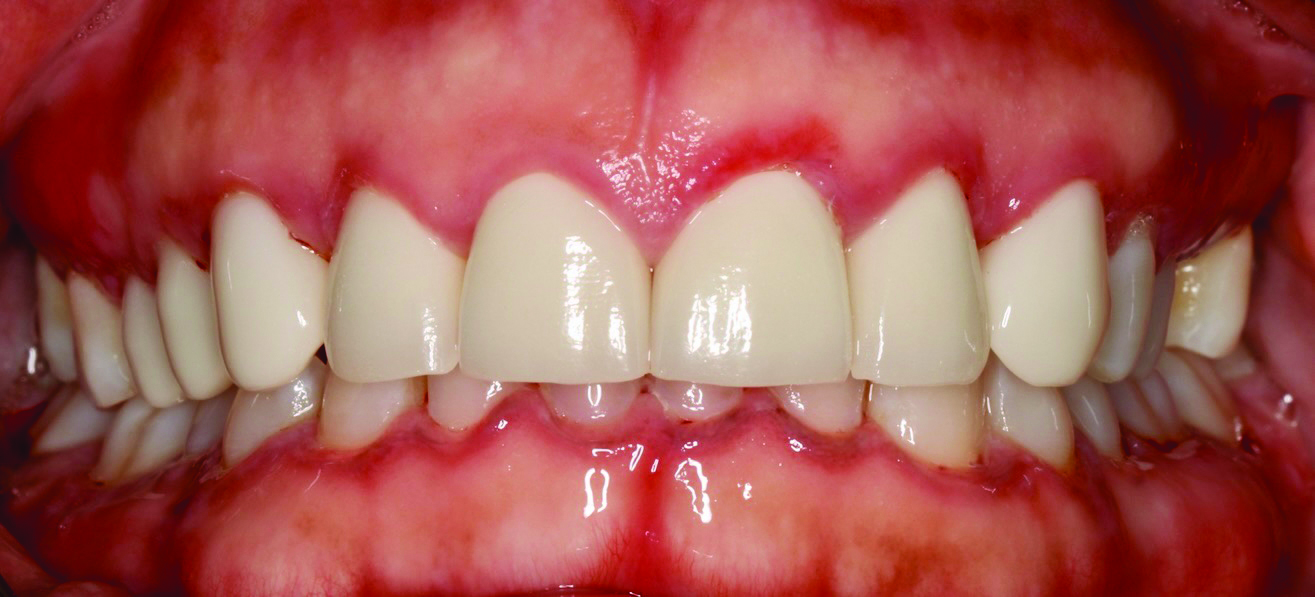

MMP is a chronic, immune-mediated disorder affecting mucous membranes.9 It predominantly affects middle-aged females, commonly presenting as painful, erythematous, ulcerated gingiva.8 The oral mucosa, especially the gingiva, is the most frequently affected site, although ocular, nasal, pharyngeal, and genital mucosa may also be involved (Figure 2). Symptoms range from mild lesions to severe systemic disease.9 Oral signs include bullae that rupture into ulcers, DG, and mucosal scarring.9 In addition to oral MMP presentation, ocular symptoms are also frequently observed. Ocular MMP may present with chronic conjunctivitis, burning, irritation, photophobia, and excessive tearing.9 In extensive MMP cases, esophageal or laryngeal involvement and subsequent scarring may cause stenosis, strictures, or airway obstruction.2

Fig 2. Mucous membrane pemphigoid in a 76-year-old Caucasian female patient. Erythematous desquamative lesions were present in both the maxilla and mandible on the gingival tissues. This patient presented with intermittent development of desquamation throughout the keratinized gingiva and reported discomfort associated with ulcerations and desquamation. The patient was sensitive to friction, including oral hygiene measures and mastication.